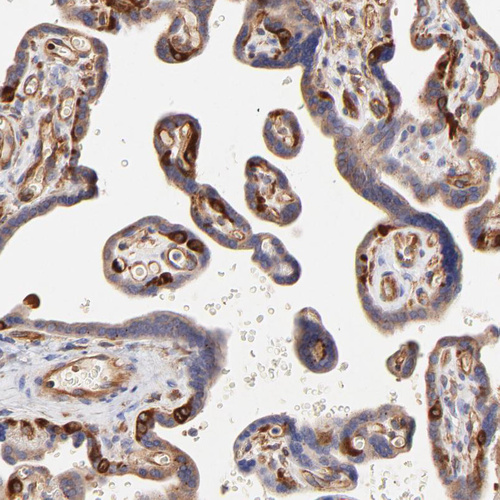

Immunohistochemistry analysis in human small intestine and skeletal muscle tissues using HPA003326 antibody. Corresponding CD2AP RNA-seq data are presented for the same tissues.